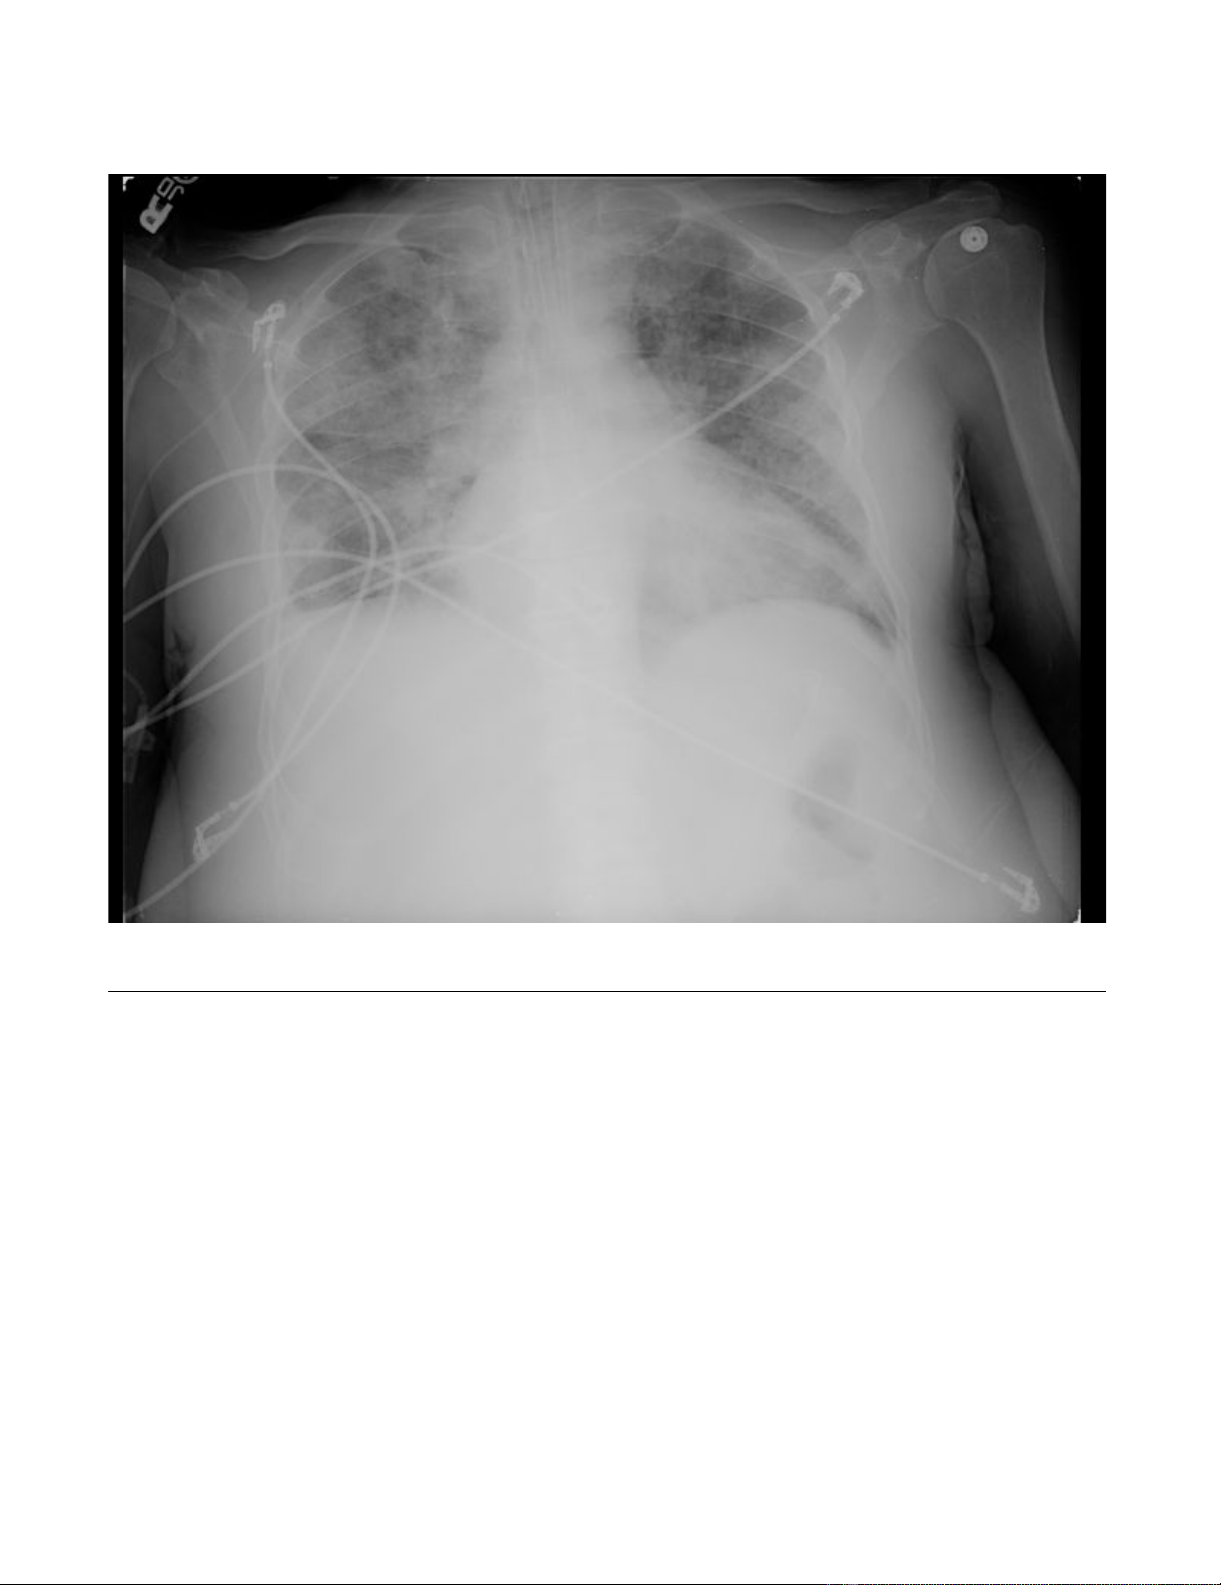

and diffuse T wave flattening. His chest X-ray demon-

strated mild cardiomegaly and evidence of pulmonary

edema. An echocardiogram conveyed a hyperdynamic left

Chest X-rayFigure 2

Chest X-ray. Cardiomegaly with diffuse bilateral interstitial infiltrates and a right-sided pleural effusion.